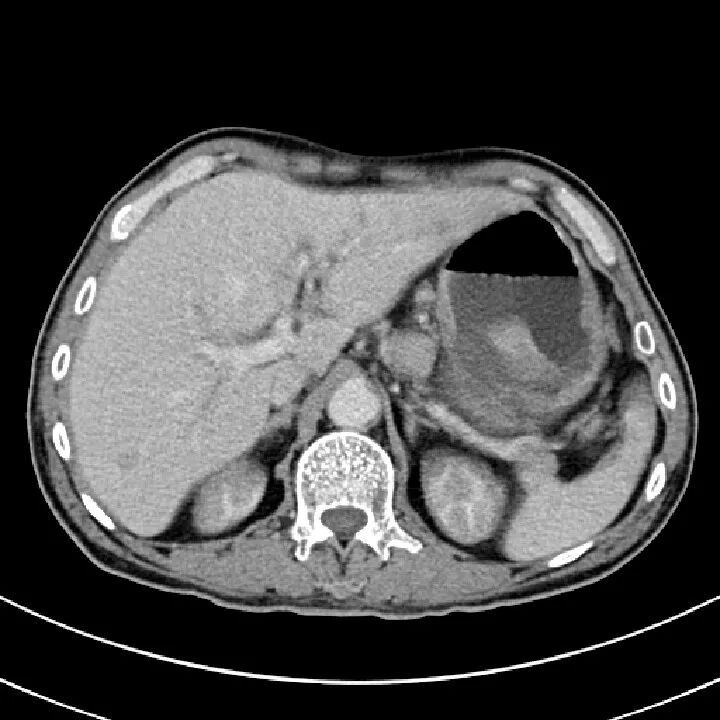

脾挫裂伤

病因病理

脾挫裂伤主要是指腹部受到外在力量的撞击而产生的闭合性损伤,是常见的腹部严重创伤,多由高处坠落、交通意外等引起。

临床表现

患者可有患部疼痛,但严重者多以失血性休克、腹部膨隆为首发症状。